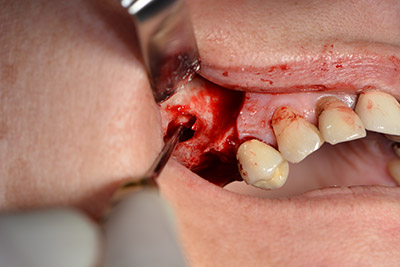

The classic incision (crestal, buccal relief) and the preparation of the mucoperiosteal flap enabled a good overview.

Sky implants (bredent) were used this case. The surgical protocol of these, specify pilot drilling at about 1200 rpm (Fig. 9).

The following holes were drilled at a reduced speed of 300 rpm. The Implantmed demonstrated its true capability at this stage. The surgical protocol can be preset – the various positions can be selected simply by pressing the “P” position of the foot control (Fig. 10 to 11).